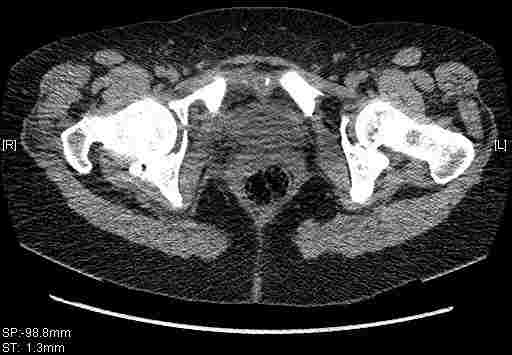

Удалось сегодня вывести пациентку в соседнюю больницу, где есть кт. Срезы сделаны только горизонтальные.